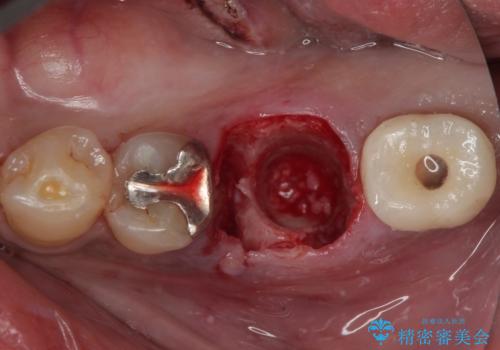

従来のインプラント治療ですと、抜歯をしてからその部分の骨が回復するまで数か月待機し、その後インプラント埋入、生着を待って土台の頭出し手術、仮歯の装着となるため、咬合回復するまでに半年かそれ以上の期間が必要となってしまいます。

咬合力の影響で歯が壊れてしまう方の場合、長期間欠損が続くと、連鎖するように他の歯が壊されてしまうリスクがあるため、抜歯即時インプラントにより、治療期間の短縮を図ることとしました。

治療は順調に進み、わずか3ヶ月でセラミッククラウンを装着することができました。